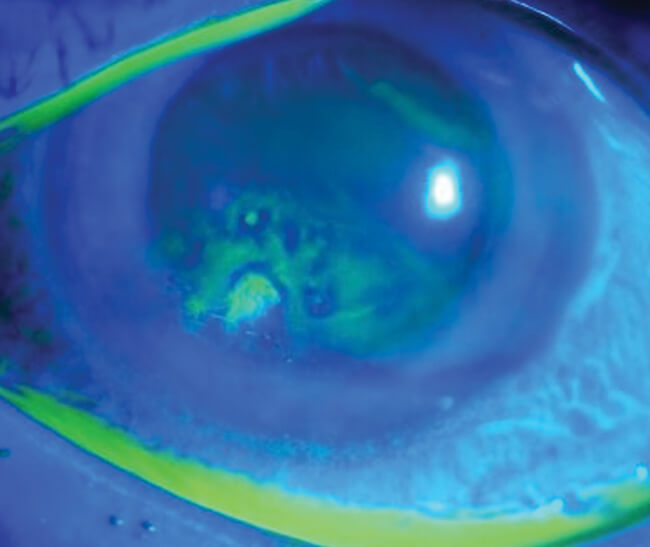

Figure 2: Fluorescein staining showing abnormal uptake suggestive of recurrent corneal erosion [16].

A 29-year-old woman awoke with a painful, red, watery left eye. The patient self-medicated with over the counter Hypromellose eye drops, every 30 minutes for one day, which resolved her symptoms. She did not seek any further medical attention. Two months later, the patient experienced the same symptoms, and presented to eye casualty. Slit-lamp examination with fluorescein staining, showed a left eye, 4mmx4mm corneal erosion. History noted the patient was taking Roaccutane (brand name of Isotretinoin) 80mg once daily, for four months. She was advised to use a hot compress every day, prescribed Hypromellose eye drops, VitA-POS eye ointment, and had follow-up in four weeks.

Within these four weeks, the patient had a further two episodes of waking overnight with left eye pain which resolved, on average, in 10 minutes. In the follow-up clinic, slit-lamp examination measured the erosion at 2.5mmx2.0mm with no infiltrate on the left cornea anteriorly, no anterior chamber reaction nor corneal oedema. The patient was advised to continue with regular Hypromellose and VitA-POS and in addition, Chloramphenicol eye drops, three times daily, for three days. Anterior stromal puncture and phototherapeutic keratectomy with excimer laser were discussed as treatment options, if symptoms persisted.